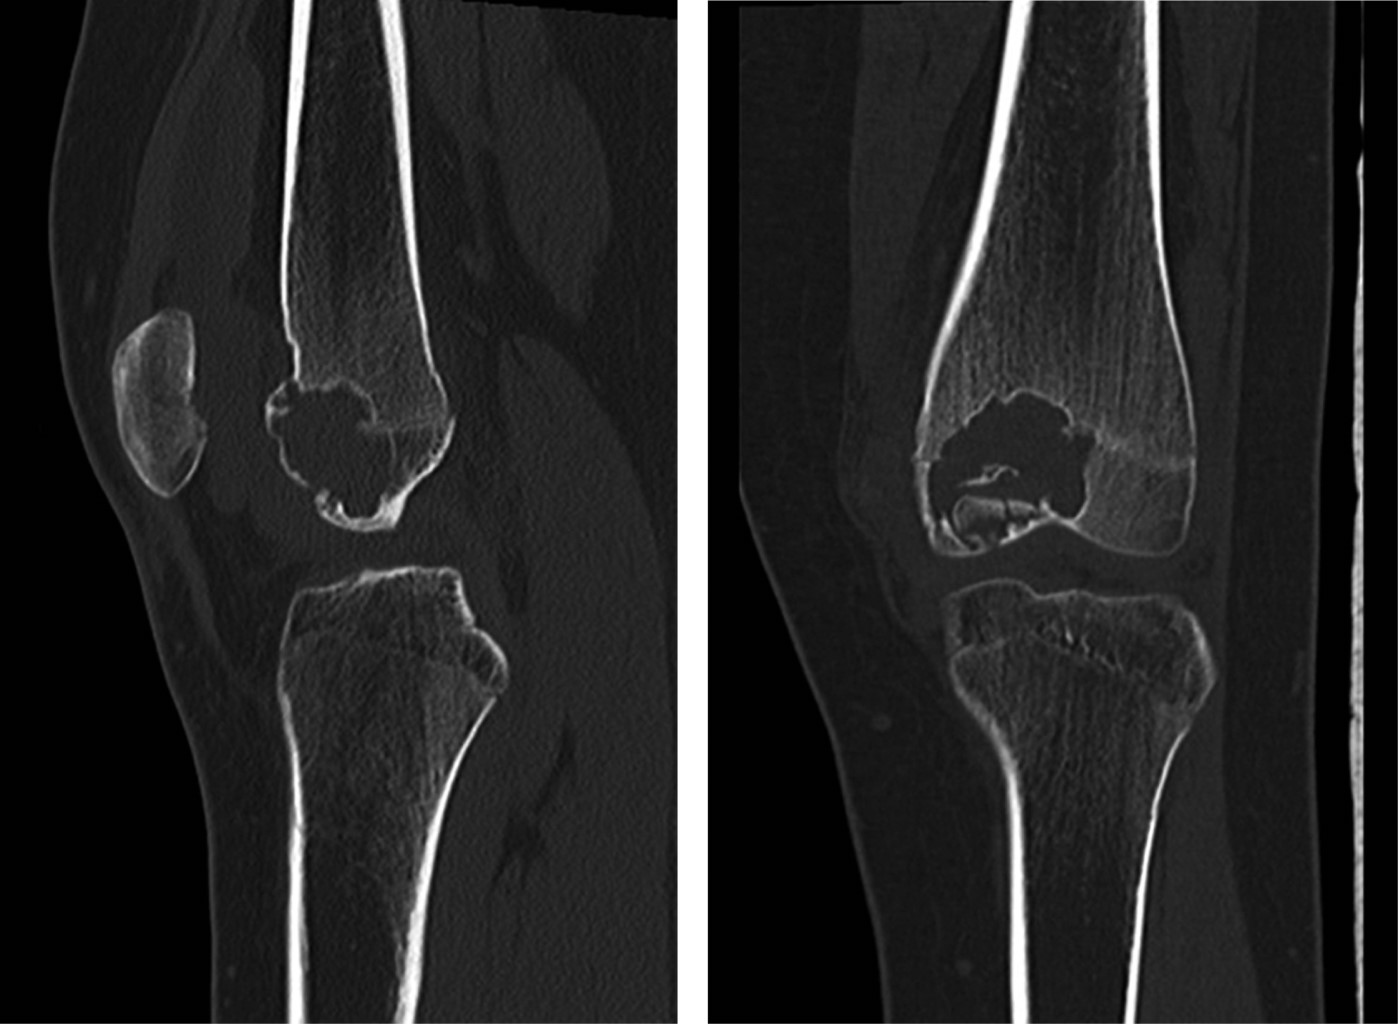

La paciente se mantuvo, posterior a la segunda intervención, sin nuevos síntomas, con controles radiológicos periódicos, sin nuevos hallazgos. Consultó a los tres años postoperada por dolor anterior de rodilla, sin antecedente de trauma, describiéndose una rodilla estable, sin aumento de volumen ni de temperatura local, con dolor ubicado en relación a la articulación patelofemoral. Se tomaron imágenes radiográficas y TAC de rodilla izquierda en las que se muestra la presencia de una lesión quística postoperatoria en región metafisaria, no sugerente de recidiva (Figuras 6 y 7). Este cuadro se manejó de manera efectiva con fisioterapia enfocada en fortalecimiento muscular y propiocepción.

Por última vez, consulta a los 20 años, cinco años posterior a la primera cirugía, por molestias en relación a rodilla izquierda, específicamente en la articulación patelofemoral. Sin signos de alarma descritos. Se tomaron radiografías, sin evidencias de recidiva ni de complicaciones. Se observó un defecto óseo en la zona de recidiva, compatible con el curetaje realizado previamente (Figura 8).

Figura 6

Figura 7

Figura 8